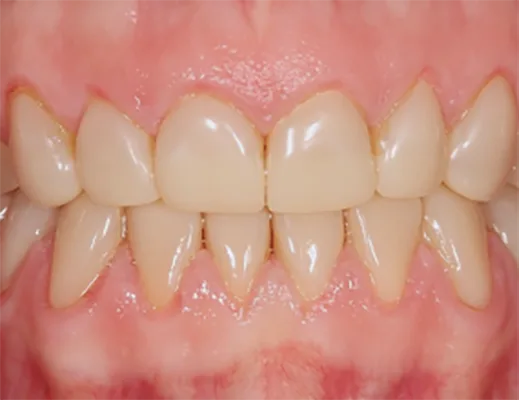

Schritt 3: Praxis – die Eingliederung

Das Einsetzen definitiver gedruckter Restaurationen aus polymeren Werkstoffen sollte adhäsiv erfolgen. Grundsätzlich empfiehlt es sich, bei der adhäsiven Befestigung die Produkte eines Herstellers zu verwenden, um Fehler hinsichtlich der Kompatibilität der einzelnen Produkte zu vermeiden. Restauration und Zahnhartstubstanz sollten entsprechend vorbereitet werden. Zur Verbesserung des Verbundes empfiehlt sich die selektive Schmelzätzung. Die Vorbehandlung gedruckter Restaurationen mit Aluminiumoxid zeigt erhöhte Verbundfestigkeiten [14]. Abbildung 3 zeigt eine Übersicht für die adhäsive Befestigung gedruckter polymerer Restaurationen.